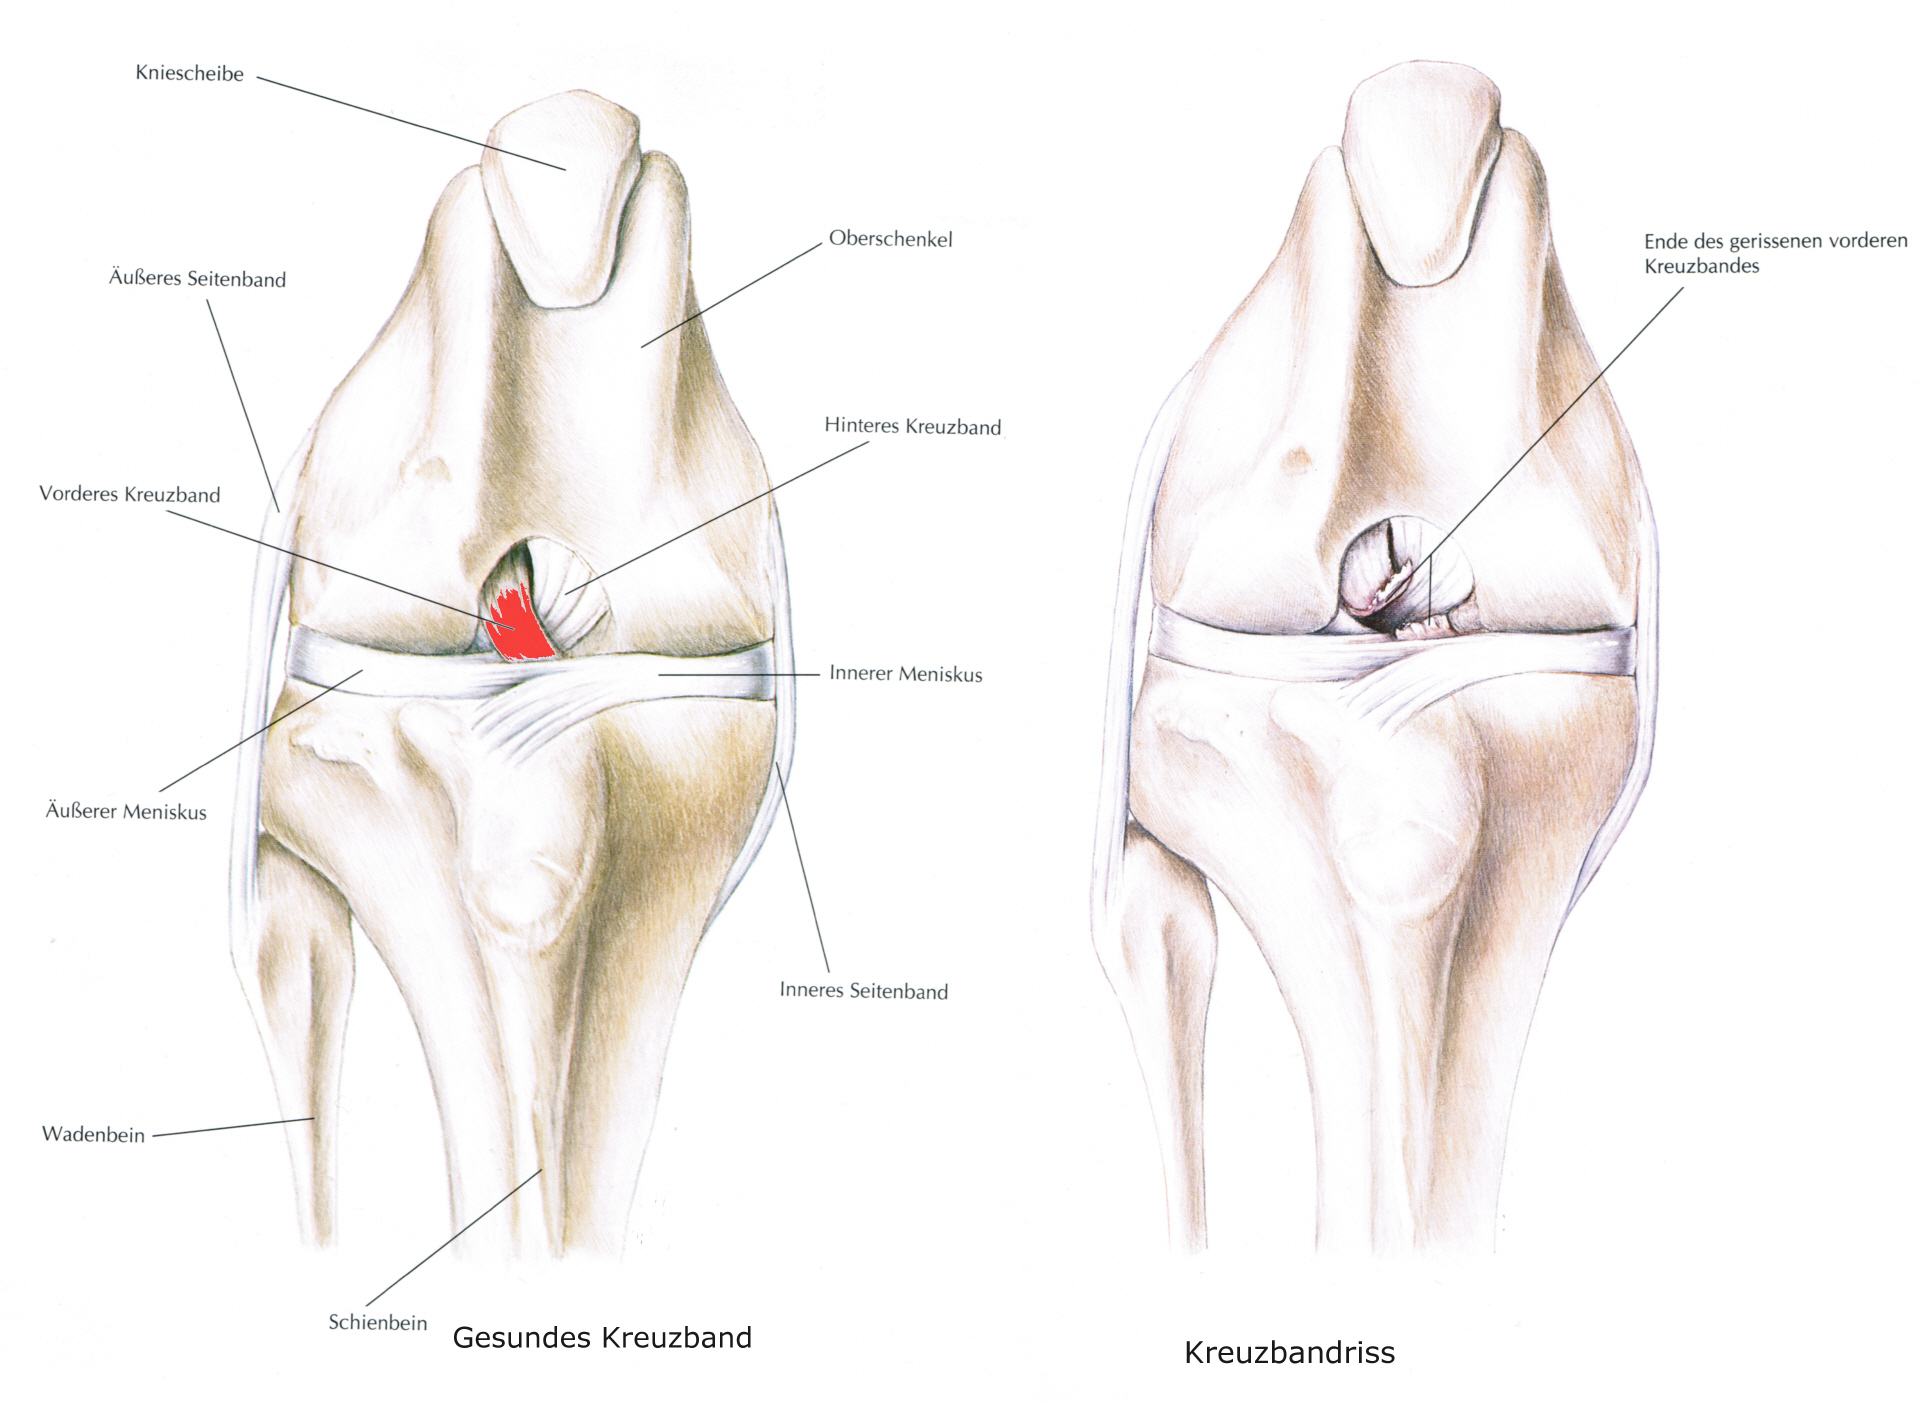

Kreuzbandriß allgemein

Der Kreuzbandriß beim Hund ist im Gegensatz zum Menschen in 90 % der Fälle nicht durch einen Unfall verursacht sondern eine Folge von degenerativen Prozessen im Gelenk wie z. B. einer Gelenksarthrose. Begünstigt wird diese Erkrankung z. B. durch Übergewicht. Deshalb geht der betroffene Hund meistens ohne deutlich erkennbare Ursache plötzlich lahm. Beim Neufundländer und Boxer ist eine genetische Anlage bewiesen. Generell gilt aber, dass vor allem ältere kastrierte Hündinnen (> 6-7 J) mit Übergewicht betroffen sind. Die betroffenen Tiere zeigen eine zumeist deutliche Lahmheit am betroffenen Hinterbein. Die Diagnose wird beim Tierarzt durch eine Ganganalyse, den Sitztest, eine umfassende klinische Untersuchung (z. B. Schubladenphänomen, Tibiakompressionstest) und Röntgendiagnostik gestellt. Eine Röntgenuntersuchung in mind. 2 Ebenen ist zwingend erforderlich um weitere Erkrankungen (z.B. eine Arthrose oder eine OCD) festzustellen.